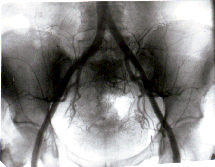

При изменении направления микроциркуляции в злокачественных

опухолях различного гистогенеза наблюдаются различные эффекты

в зависимости от показателей интенсивности фильтрации. При ее

10-кратном возрастании опухолевая ткань подвергается трансформации

в кость (Рис. 1, 2, 3, 4). При 20-крат-ном - опухолевые

клетки подвергаются некробиозу, в ранее аваскулярных зонах возникают

капиллярные сети, опухоль изолируется от окружающих тканей, она

сокращается в размерах более чем на 50% от исходных, исчезают

осложнения: кровотечения, боли и др.